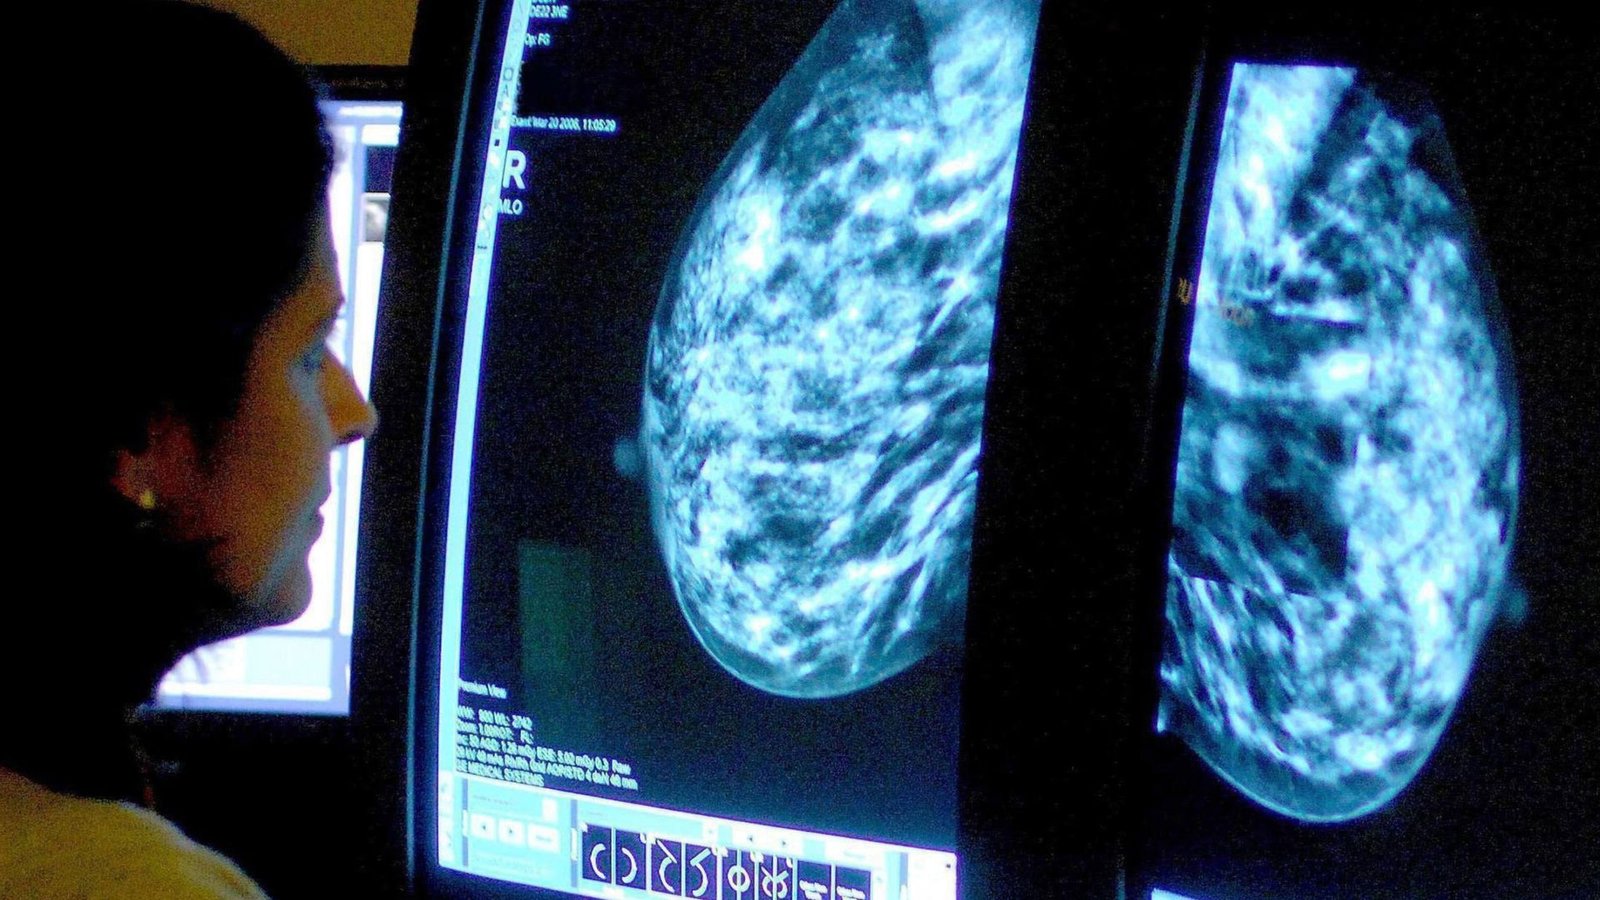

Image:

AI could help reduce radiologists’ workload and cut waiting times. Pic: iStock